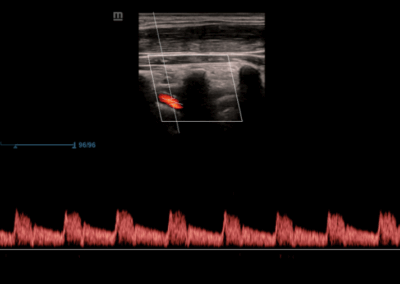

Los sistemas ecográficos estándares disponibles en la actualidad generalmente permiten un diagnóstico básico, pero carecen de funcionalidades avanzadas. Ahora, el DC-30 FullHD es la respuesta perfecta para un rendimiento de imagen de alta calidad, con una pantalla táctil de 21,5 pulgadas y funciones avanzadas como Auto IMT, iScape, elastografía Natural Touch, imágenes con contraste UWN e imágenes Doppler tisulares en el ámbito de las imágenes generales, y Smart OB, Smart face e iLive en el ámbito de la obstetricia.